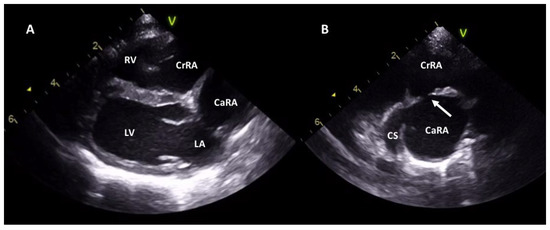

2.2. Case 2